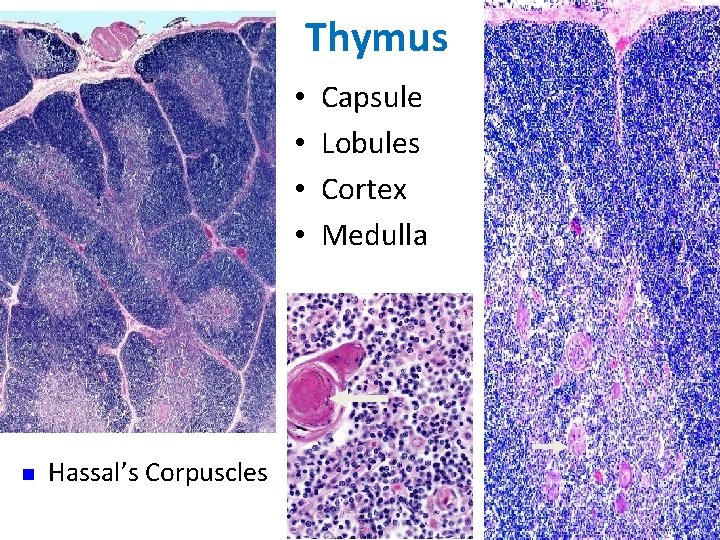

Thymus is the only discrete central lymphoid organ in humans. It produces only T lymphocyte precursors and has no lymphoid nodules. Its reticular cells derive from endoderm and produce no reticular fibers. It is the only organ containing Hassall’s corpuscles. Its age-dependent structural atrophy or involution is also unique among lymphoid organs. 2 lobes are joined and covered by a thin loose connective tissue capsule that penetrates the lobes as septa, dividing each lobe into incomplete lobules. Cortex. This is the dark-staining periphery of each lobule. Small lymphocytes predominate

Medulla. In effect, each thymic lobe has a single medulla that extends into the core of each of the lobules. The light staining of the medulla reflects the presence of more epithelial reticular cells and fewer lymphocytes than in the cortex. The spheric Hassall’s corpuscles (30 -150 m in diameter) are composed of concentric layers of flattened epithelial reticular cells. With age, cells in the core of the corpuscles may die and calcify. Functions: 1. T lymphocyte production. 2. Blood -thymus barrier. 3. Production hormone - thymosin

Thymus • • n Hassal’s Corpuscles Capsule Lobules Cortex Medulla